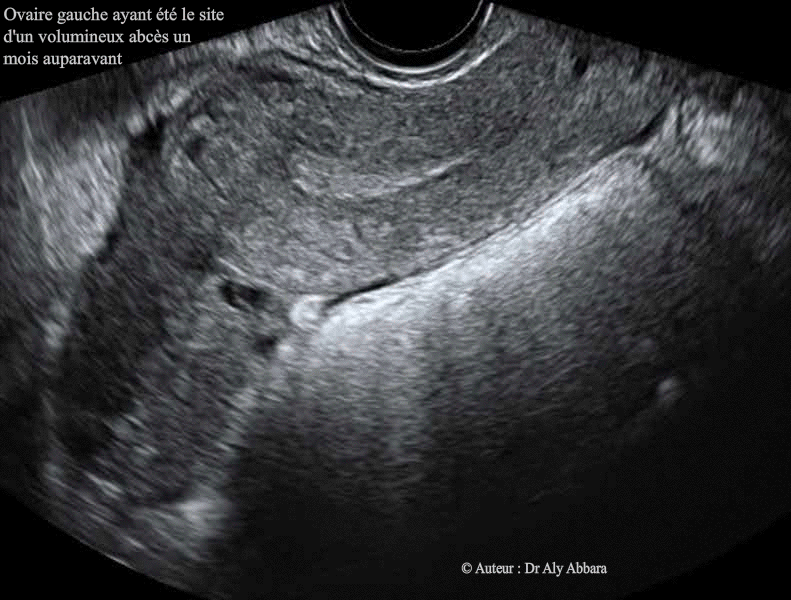

Image animée montrant l'aspect échographique d'un ovaire gauche qui fut, un mois auparavant, le site d'un volumineux abcès associé à une salpingite aiguë homolatérale. Cette infection génitale haute aiguë a nécessité un drainage chirurgical et une administration d'une triple antibiothérapie pendant trois semaines. |

| Histoire de maladie : Dans un contexte d'infection abdomino-pelvienne, sur des images échographiques, on met en évidence la présence d'une formation kystique intra-ovarienne gauche mesurant 74 x 56 x 71 mm (soit 155 cm3), uniloculaire, à contenu hypo-échogène avec un aspect de niveau faisant penser à la présence d'un contenu liquidien à deux niveaux de densité. Les structures ovariennes entourant cette formation ovarienne kystique paraissent épaissies, infiltrées et contenant des multiples petites formations kystiques satellites. Échographiquement, l'ovaire droit est normal, avec un volumineux hydrosalpinx droit. Cliniquement, on note la présence d'une masse palpable dans la région sous ombilicale, de 8 à 10 cm de diamètre, légèrement sensible, chez une patiente âgée de 28 ans, souffrant d'une douleur abdominale sous ombilicale, évoluant depuis une semaine, sans hyperthermie, mais biologiquement on note la présence d'une hyperleucocytose à 14 giga/l, et CRP à 186 mg/l et enfin, une anémie inflammatoire à 7 g/dl. Le scanner abdomino-pelvien confirme la présence de masse à cavité uniloculaire en position très haute, surplombant le fond utérin et au contact avec la paroi abdominale antérieure, dans la région qui se trouve au-dessous de l'ombilic. Au voisinage de l'ovaire gauche abcédé, on remarque la présence d'une autre formation oblongue, à paroi infiltrée, avec dans son centre, une collection liquidienne ; il s'agit de la trompe gauche inflammatoire avec petit pyosalpinx. Le diagnostic évoqué est celui d'une infection génitale haute gauche comportant un abcès ovarien et un pyosalpinx gauches. Le diagnostic définitif a été réalisé suite à la réalisation d'une laparotomie : volumineux ovaire gauche abcédé et collant fortement, par des adhérences, anciennes denses et fibreuses, à la paroi abdominale antérieure et aux anses grêles juxtaposées. La cavité de l'ovaire est suppurée, ainsi les multiples formations folliculaires satellites, intra-ovarienne. La trompe gauche est très inflammatoire à contenu suppuré (pyosalpinx). L'ovaire droit est normal. La trompe droite est caractérisée par la présence de multiples signes macroscopiques de salpingite ancienne (non aiguë) : obturation l'ostium tubaire externe ; un volumineux hydrosalpinx et multiples voiles adhérentiels. Le cul-de-sac postérieur est bloqué par de vieilles adhérences fibreuses. L'image présentée dans cette page, montre l'aspect de cet ovaire gauche un mois plus tard, où on note la disparition complète de la cavité abcédée intra-ovarienne gauche. |